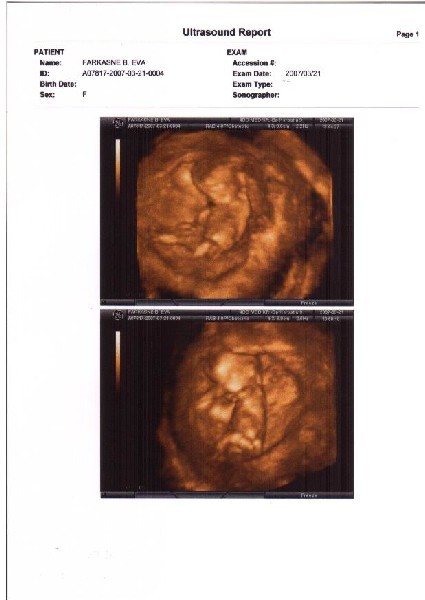

a hétvégén jelentjük be a szüleimnek, anyósom már tudja,a dolgozóban meg jövőhéten mondom a főnökömnek...kíváncsi leszek a reakciókra...